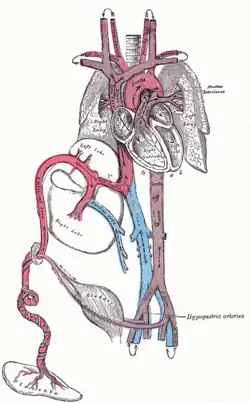

Плацентарный круг кровообращения

Существует у плода, находящегося в матке.

Кровь матери поступает в плаценту, где отдаёт кислород и питательные вещества капиллярам пупочной вены плода, проходящей вместе с двумя артериями в пупочном канатике. Пупочная вена даёт две ветви: бо́льшая часть крови поступает через венозный проток напрямую в нижнюю полую вену, смешиваясь с неоксигенированной кровью от нижней части тела. Меньшая часть крови поступает в левую ветвь воротной вены, проходит через печень и печёночные вены и затем также поступает в нижнюю полую вену.

После рождения пупочная вена запустевает и превращается в круглую связку печени (ligamentum teres hepatis). Венозный проток тоже превращается в рубцовый тяж. У недоношенных детей венозный проток может функционировать в течение некоторого времени (обычно рубцуется через некоторое время. Если нет — существует опасность развития печёночной энцефалопатии). При портальной гипертензии пупочная вена и аранциев проток могут реканализироваться и служить путями обходного кровотока (порто-кавальные шунты).

По нижней полой вене течёт смешанная (артериально-венозная) кровь, насыщение которой кислородом составляет около 60 %; по верхней полой вене течёт венозная кровь. Почти вся кровь из правого предсердия через овальное отверстие поступает в левое предсердие и, далее, левый желудочек. Из левого желудочка кровь выбрасывается в большой круг кровообращения.

Меньшая часть крови поступает из правого предсердия в правый желудочек и лёгочный ствол. Так как лёгкие находятся в спавшемся состоянии, давление в лёгочных артериях больше, чем в аорте, и практически вся кровь проходит через артериальный (Боталлов) проток в аорту. Артериальный проток впадает в аорту после отхождения от неё артерий головы и верхних конечностей, что обеспечивает их более обогащённой кровью. В лёгкие поступает очень малая часть крови, которая в дальнейшем поступает в левое предсердие.

Часть крови (около 60 %) из большого круга кровообращения по двум пупочным артериям плода поступает в плаценту; остальная часть — к органам нижней части тела.